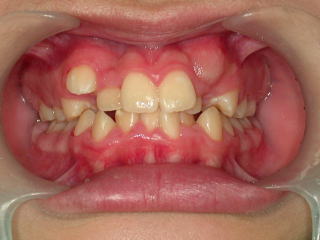

平成19年5月19日 安定してきました。

初診平成18年3月4日 現在平成19年5月19日